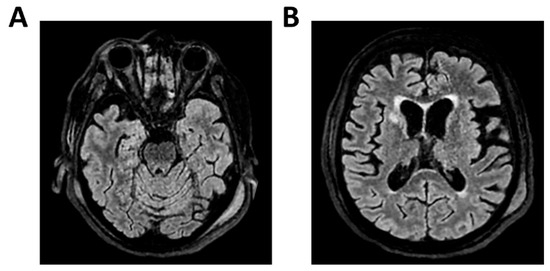

Background: Meningoencephalitis is a complex inflammatory condition of the CNS that can result in significant morbidity and mortality in critically ill adults. Accurate and timely neuromonitoring is essential for guiding management and improving outcomes. This study aimed to descriptively evaluate the prognostic value of early TCCD monitoring, particularly the pulsatility index, and its integration with conventional and perfusion MRI in patients with meningoencephalitis. Methods: We present an observational, retrospective, cohort study involving ten adult patients (median age 56 years, IQR 45.5–68.5; mean 55.9, range 35–76) with neurological syndromes caused by suspected or confirmed infectious meningoencephalitis. Etiologies included bacterial meningitis/meningoencephalitis (50%), viral meningoencephalitis (10%), neurotoxoplasmosis (10%), progressive multifocal leukoencephalopathy (10%), and undetermined origin (20%). Patients underwent TCCD and MRI within 24 h. In five cases, standard MRI sequences were acquired, while in the remaining five, perfusion imaging was performed using Arterial Spin Labelling (ASL). A favorable outcome was defined as survival with neurological recovery (Glasgow Outcome Scale > 5) at ICU discharge. Results: TCCD-derived PI provided valuable information on cerebral hemodynamics. PI values ≤ 1.25 were associated with favorable clinical outcomes and symmetrical MRI findings. Conversely, PI > 1.25 correlated with poor prognosis and often preceded MRI-detectable structural damage. When combined with ASL, PI mirrored the detected perfusion asymmetries and was associated with poor prognosis in fatal cases. Conclusions: Bedside TCCD can offer real-time assessment of cerebrovascular dynamics and, when integrated with conventional and ASL MRI, could enhance the understanding of pathophysiological processes in meningoencephalitis, supporting timely and informed decisions in neurocritical care.